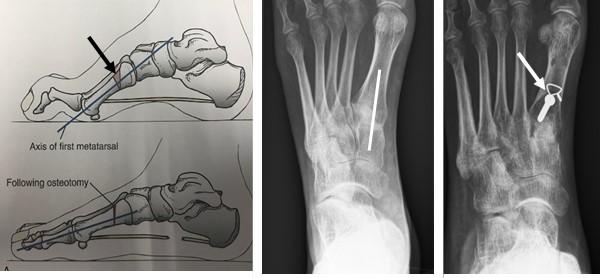

SPLATT (Split anterior tibial tendon transfer)

De SPLATT, of ½ tibialis anterior transpositie, omhelst het verplaatsen van de helft van de tibialis anteriorpees naar de buitenzijde van de voet. Hiermee wordt wederom een kracht van de binnenzijde naar de buitenzijde van de voet verplaatst om de balans te verbeteren. De verplaatste pees wordt meestal vastgehecht aan de peroneus tertiuspees die aan de voor-buitenzijde van de enkel/voet loopt en de voet naar buiten en omhoog beweegt.

Figuur 3: De tibialis anteriorspier. Bij het streepje op het linkerplaatje komt een litteken waar de helft van de pees wordt losgemaakt. Dat stukje pees “tunnelen” we naar net boven de enkel (2e plaatje). Dan verplaatsen we dat stukje pees naar de buitenzijde van de voet (streepje op 3e plaatje) en hechten deze vast aan de peroneus tertiuspees. Op het meest rechtse plaatje staat de eindsituatie waarbij de pees voor de helft naar de buitenzijde van de voet is verplaatst en de balans is veranderd.